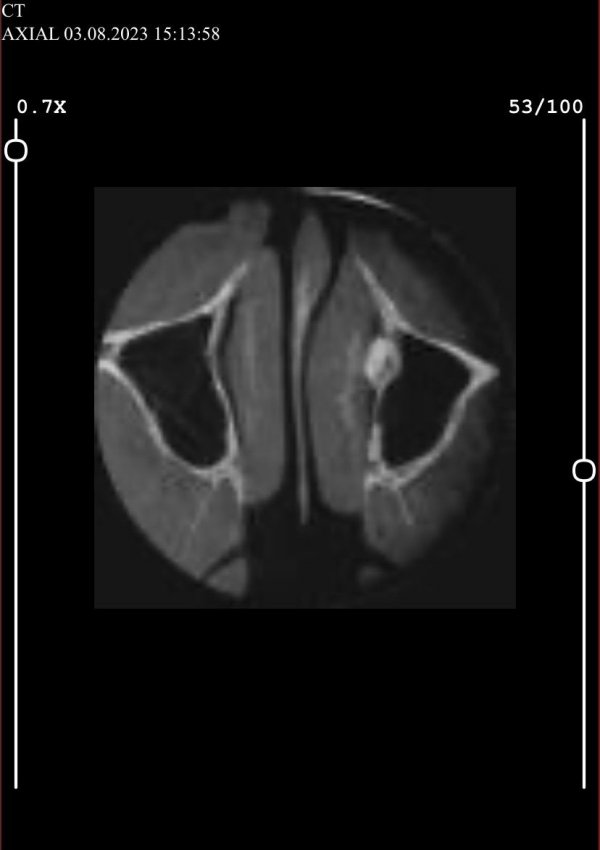

Kendisine burun sinüs zarının yırtıldığını, burun kanalından içeriye çekilen diş kök kemiğinin kaçtığını ve damağında 8.5 mm sinüsün kaldığını söylendiğini aktaran Bulut, “Şunu öğrendim ki, diş hekimlerinin bu ameliyatı yapmaya yetkisi yokmuş. Bu işlemin bir çene cerrahı tarafından yapılması gerekiyormuş. Şimdi bir kez daha ameliyat olmam gerekiyor.” ifadelerini kullandı.